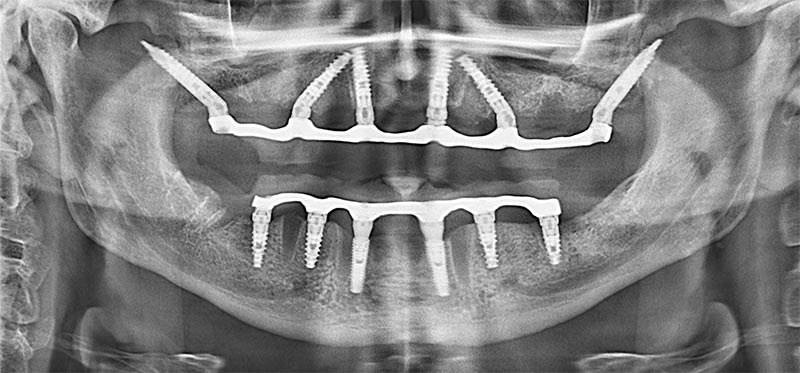

Имплантация 2-х челюстей по методике все на 6

Была предложена методика протезирования зубов на 6 имплантатах. В верхнюю челюсть были вкручены 6 израильских имплантатов Noris Medical. На нижней челюсти ситуация был несколько иной. Поэтому использовалась комбинация из 4 тех же израильских имплантатов + 2 южно корейских Megagen.